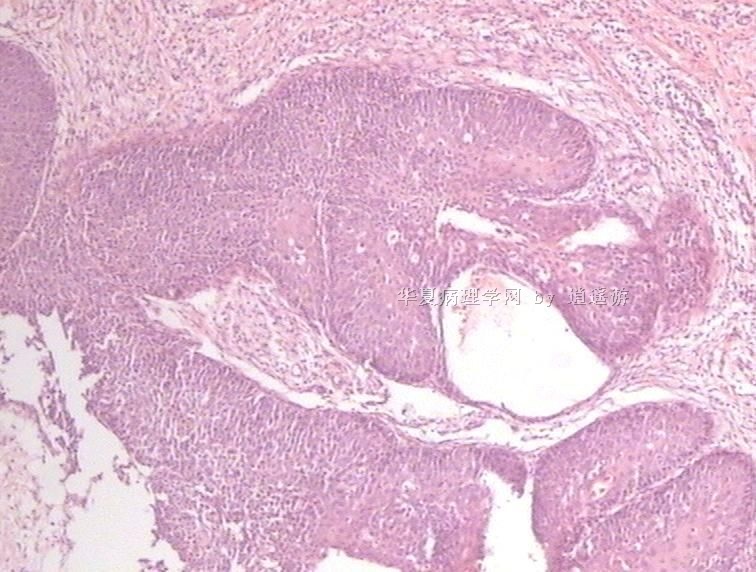

姓    名: ××× 性别:  女 年龄:  40

标本名称:  宫颈leep环切术切除组织

简要病史:  宫颈Ⅲ度糜烂

图1、2,10×,图3-6,4×,图7、8,40×

设备不够好,图像较模糊。

CIN3级累腺。

多看看是否有浸润,以及切缘。

CIN3级累腺,切缘是否干净?

CIN3级累腺

未见到浸润,但边缘看起来未切净。

同意.

很典型的.